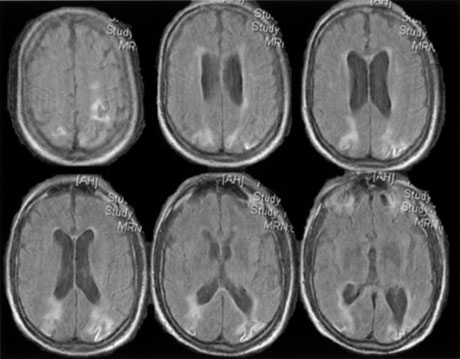

OPTIC TRACTS The optic tract is the continuation of the anterior visual system from the optic chiasm to the LGN. Only the contralateral hemifield is represented. The decussated nasal retinal fibers are not initially well aligned topographically with the other eye's temporal retinal fibers, but retinal correspondence improves towards the termination of the tract at the lateral geniculate nucleus (LGN). The retinotopic map is also tilted in the optic tracts, so that the macula is represented dorsally, inferior retina (superior visual field) laterally, and superior retina (inferior visual field) medially (see Chapter 4, Fig. 9).1 The magnocellular and parvocellular axons also may be segregated, with magnocellular axons more ventral.2 Both of these topographies are mirrored in the LGN. The main vascular supply of the optic tract is the anterior choroidal artery. The functional anatomy of the optic tract is reflected in several important clinical findings. First, partial lesions cause contralateral homonymous defects that can be markedly incongruous (different patterns of visual loss in the two eyes) because of the poor topographic alignment of the two retinal maps (Figs. 1 and 2).3,4 In contrast, lesions of the optic radiations cause only mild incongruity and striate lesions are highly congruous. Complete transection of the optic tract leads to congruous complete hemianopia, although this is less frequent than partial lesions. Reduced acuity with an optic tract lesion indicates bilateral tract damage or extension of the lesion to the optic chiasm or optic nerves.4,5 Second, because the axons in the optic tract originate from retinal ganglion cells, damage to the tract causes optic atrophy over time. This is present in both eyes, but because only half or less of the axons of each eye are affected, the atrophy is less severe than with most optic neuropathies. Also, the pattern of optic atrophy differs between the eyes. In the eye with temporal field loss, the axons from the nasal retina are affected. The fibers from the nasal periphery enter the nasal side of the disc, whereas those from the nasal macula enter the temporal disc in the papillomacular bundle. Atrophy is seen in these nasal and temporal wedges of the disc but the superior and inferior sectors are spared, because these contain fibers from the temporal retina. The result is “bow-tie” optic atrophy (see Fig. 1). In contrast, atrophy in the eye with nasal field loss affects the superior and inferior wedges and papillomacular bundle, but not the nasal wedge. This appears as diffuse or temporal disc pallor. Another distinctive optic disc picture occurs in the eye with temporal field loss when a mass lesion causes papilledema and compresses the optic tract. Disc swelling occurs in the superior and temporal disc but not in the atrophic bow-tie regions, creating “twin-peaks” papilledema (see Fig. 2).6,7 Third, because fibers for the pupillary reflex also travel in the optic tract, often there is a relative afferent pupillary defect (RAPD). With a significantly incongruous hemianopia, the RAPD may be in the eye with greater visual loss. With a complete tract lesion the RAPD is in the eye with temporal field loss,4,8 because the temporal hemifield is larger and there are slightly more axons from the nasal than temporal retina (ratio 53:47). The RAPD is a useful sign in optic tract hemianopia because it may be present at a time when optic atrophy has not yet developed (see Chapter 15).9 Other reported pupillary abnormalities include Wernicke's hemianopic pupil, which is an intraocular afferent pupil defect, with less pupillary constriction from light on the hemianopic hemiretina compared to light on the intact hemiretina. Wernicke's hemianopic pupil is difficult to elicit at the bedside because of intraocular light scatter,3 although it may be seen with computerized pupillometry (Fig. 3). The combination of optic atrophy, RAPD and field incongruity is important to recognize with homonymous hemifield defects, because it changes the differential diagnosis of hemianopia (Fig. 14). Most hemifield defects from lesions of striate cortex or the optic radiations result from vascular disease or other intracerebral pathology. Most optic tract lesions are compressive extrinsic masses, with a differential diagnosis similar to that for optic chiasmal lesions (see Chapter 6). In fact, patients with combined damage to the optic tracts, chiasm, and nerve are not rare.4,10–13 Pituitary adenomas, giant aneurysms of the internal carotid artery, meningiomas, and craniopharyngiomas are the chief causes of optic tract dysfunction. The investigation of choice is imaging of the parasellar region, with coronal and axial sections and contrast administration. Less common lesions include inflammatory conditions such as multiple sclerosis3,11,14,15 and sarcoidosis (see Fig. 1).16 Intrinsic optic pathway gliomas may occur in the optic tracts. Vascular lesions are rare, but there are reports of cavernous angiomata10,17 or arteriovenous malformations.18 Optic tract infarction can complicate anterior temporal lobectomy, possibly from vasospasm of the anterior choroidal artery.19 Trauma can affect the optic tract.3 Radiotherapy of pituitary tumors may be followed years later by optic tract necrosis.13 Optic tract dysfunction is a side effect of alpha-interferon.20 On occasion there is congenital absence of the optic tract 21; such patients are often unaware of their hemianopia. Associated abnormalities are unusual.3 These include endocrine disturbances from hypothalamic dysfunction and memory impairment from temporal lobe involvement,22 reflecting the proximity of the optic tracts to these structures (see Chapter 4). LATERAL GENICULATE NUCLEUS The LGN is a subnucleus in the ventro-postero-lateral corner of the thalamus. Neighboring thalamic subnuclei include the medial geniculate nucleus ventromedially, ventral posterior nucleus dorsomedially, and pulvinar superiorly and dorsally. The medial geniculate nucleus gives rise to the acoustic radiations, which pass by the dorsomedial aspect of the LGN on their way to the auditory cortex in the temporal lobe. The optic radiations arise from the dorsolateral surface of the LGN. Ventrally, the hippocampus and parahippocampal gyrus face the LGN across the ambient cistern and the inferior horn of the lateral ventricle. The LGN has a dual blood supply: the anterior choroidal artery, a branch of the internal carotid artery, and the lateral choroidal artery, a branch of the posterior cerebral artery. The anatomy of the vascular territories within the LGN has been debated. Initial studies suggested that the anterior choroidal artery supplied the medial LGN as well as the optic tract and the lateral choroidal artery the lateral LGN. However, experience with surgical arterial lesions concluded that the anterior choroidal artery supplied both the lateral and medial aspects and the lateral choroidal artery supplied the hilus and midzone of the LGN. In addition to its function as a relay in the visual pathway, the LGN is also a site of modulation, by back-projections from visual cortex23,24 and afferent projections from the brainstem reticular formation and superior colliculus.25 Some of the corticofugal input influences the stimulus selectivity of LGN neurons.24 Others postulate that these nonretinal inputs play a role in gating visual transmission through the LGN, and thus participate in selective attention.23 The LGN is a triangular shaped structure with six roughly horizontal layers containing segregated inputs from the two eyes (see Chapter 4, Fig. 8). The ventral two layers are the magnocellular layers, whereas the other four layers are the parvocellular component; these differ in many structural and functional aspects (see Chapter 4). The LGN has a retinotopic pattern that is a continuation of that found in the optic tract. The macula is represented in a dorsal wedge, including the hilum and projecting posteriorly, whereas the most peripheral fibers are located ventrally. Superior retinal fibers (contralateral inferior visual quadrant) are in the medial horn and inferior retinal fibers (contralateral superior visual quadrant) are in the lateral horn. Because the LGN is small and relatively secluded, lesions here are rare. Its intimate relation to the optic tract and optic radiation make it difficult to be certain that a visual defect results from LGN damage rather than damage to these structures. Indeed, visual field defects from purported LGN lesions resemble visual field defects from optic tract or optic radiation lesions. Three main types of hemianopic defects have been described. The first is an incongruous hemianopia, much like that seen with optic tract lesions, reflecting the continued segregation of ocular inputs in the LGN. The other two patterns are sectorial hemianopias reflecting the unusual territorial division between the anterior and lateral choroidal arterial supplies. With lateral choroidal ischemia, the hilum and middle zone of the LGN are affected, causing a wedge-shaped visual defect straddling the horizontal meridian (Fig. 4).26 With anterior choroidal ischemia, the lateral and medial tips of the LGN are infarcted, resulting in the reverse defect, loss of the superior and inferior aspects of the contralateral hemifield with sparing around the horizontal meridian.27,28 Unusual cases of presumed bilateral LGN damage have presented with an “hourglass” shape to either the visual field defect29,30 or the region of spared vision.31 Optic atrophy often accompanies LGN lesions. If there is damage to almost all of the LGN, the optic atrophy has a similar appearance to that seen with optic tract lesions. If there is partial damage causing sectorial hemianopias, then the optic atrophy may be more subtle and restricted to the relevant sectors of the disc.26,27 However, because the afferent fibers subserving the pupillary light reflex already have departed for the pretectum, there is no RAPD with lesions of the LGN. With incongruous hemianopia and optic atrophy, this is the only feature that permits distinction between optic tract and LGN lesions. A variety of pathologies have been reported with LGN lesions. Infarction is the most likely cause of sectoranopia, given the dependence of such defects on the vascular anatomy,26,27 but astrocytomas and arteriovenous malformations are also reported. Furthermore, the LGN appears to be a target of central pontine myelinolysis, a syndrome associated with excessively rapid correction of hyponatremia.29,30,32 LGN damage rarely is a parainfectious complication of traveler's diarrhea.31 OPTIC RADIATIONS The optic radiation may be affected anywhere in its course (see Chapter 4); the type of visual field defect reflects the site of damage. Ischemic or hemorrhagic lesions of the internal capsule affect the optic radiation while it is still a relatively compact bundle, usually causing a complete homonymous hemianopia. A similar defect can arise from damage close to the termination in striate cortex (Fig. 5). Lesions of the ventral fibers in the anterior temporal lobe cause a contralateral superior visual quadrant defect (Fig. 6). Most often this defect aligns on the vertical meridian, with variable extension toward the horizontal meridian and central vision.33 Lesions of the dorsal fibers in the parietal lobe cause an inferior visual quadrant defect (Fig. 7). Because there is no sharp demarcation of the dorsal fibers from the ventral fibers in this portion of the posterior pathway, the defect seldom aligns along the horizontal meridian.33 Overall, quadrantanopia is more frequent with lesions of striate cortex.33 Lesions of the temporal lobe more than 8 cm posterior to its anterior tip can affect both upper and lower radiations. Small lesions also may affect certain portions of the radiations and spare others; for example, damage to the midportion of the optic radiation can mimic the sectoranopias of LGN lesions (Fig. 8).34 Although there can be some incongruity to the visual field defects of optic radiation lesions, this is less marked than the incongruity with optic tract lesions. Unlike lesions of the retino-geniculate pathway or LGN, lesions of the geniculostriate axons do not lead to optic atrophy (with the exception of some congenital lesions, through trans-synaptic degeneration) or pupillary defects. However, frequently there are other signs of cerebral damage,33 especially if the lesion is large. Thus, temporal lobe lesions cause superior quadrantic defects and sometimes also complex partial seizures, auditory or complex visual hallucinations (some of which may be seizures), memory problems, or a Wernicke's aphasia if the dominant hemisphere is involved. Parietal lesions with mainly inferior quadrantic defects may cause cortical sensory disturbances, such as impaired two-point discrimination and graphesthesia, and impaired smooth pursuit toward the side of the lesion. With dominant hemisphere lesions, Gerstmann's syndrome (acalculia, finger anomia, right-left disorientation, and agraphia) may occur, as may a variety of aphasic syndromes, including alexia with or without agraphia, Wernicke's aphasia, or global aphasia. The differential diagnosis of optic radiation lesions reflects the variety of cerebral hemispheric pathologies. Unlike lesions of the optic tract, most are infarcts in the posterior cerebral or middle cerebral artery territories. Tumors, vascular malformations, infections, and leukodystrophies are also possibilities. The temporal profile of the illness often is the major clue to the etiology. STRIATE CORTEX The primary visual area in the medial occipital lobe goes by several names: Brodmann's area 17, “visual area 1” or V1, “calcarine cortex,” and “striate cortex” (see Chapter 4). The exact position of striate cortex varies among individuals. Although the parieto-occipital fissure forms a reasonably reliable anterior dorsal boundary, the posterior limit containing the macular representation is more variable, extending from the medial occipital surface over the first one or two centimeters of the posterior surface of the occipital lobe (see Chapter 4, Fig. 10). The main vascular supply of striate cortex derives from the posterior cerebral artery (see Chapter 4, Fig. 15). A parieto-occipital branch supplies the superior calcarine bank, a posterior temporal branch supplies its inferior bank, and a calcarine branch supplies the central region posteriorly; however, individual variation exists.35 Perhaps most importantly, the occipital pole is at the junction (watershed zone) of the vascular territories of the posterior and middle cerebral arteries, and again there is marked variation as to which artery supplies the foveal representation in striate cortex.35 The retinotopic arrangement in striate cortex is well known (see Chapter 4), and confirmed with recent imaging studies of lesions.36 The foveal representation is posterior, at the occipital pole, and the far peripheral field is anterior, on the medial occipital surface.37,38 The superior bank of the calcarine fissure receives input from the inferior visual field, whereas the inferior bank contains the representation of the superior visual field. The most anterior part of striate cortex represents the monocular temporal crescent, the region of temporal field in the contralateral eye that lies beyond the limits of the nasal field (60°) of the ipsilateral eye. As in most of the visual system, there are fewer neurons devoted to peripheral vision than to central vision: Over half of striate cortex is devoted to the central 10° (cortical magnification).36,39 Occipital cortex contains a mixture of monocular and binocular cells arranged in ocular dominance columns, but large separations between the inputs of the two eyes are not present. Visual Field Defects from Striate Lesions Focal destruction of striate cortex produces a homonymous contralateral visual hemifield defect. Unlike the scotomata from lesions of the optic radiations and especially the optic tracts, the hemianopic defects from striate lesions are highly congruent, with virtually identical defects in the two eyes. Complete destruction of striate cortex causes complete visual loss in the contralateral visual hemifield. Because this involves not only peripheral vision but also the contralateral half of the foveal region it is called a macula-splitting homonymous hemianopia. This may occur with posterior cerebral artery ischemia in a patient whose entire striate cortex is supplied by that artery. Macula-splitting hemianopias can occur with complete lesions anywhere along the retrochiasmal visual pathways, and thus lack localizing value (see Fig. 5). Other signs may help in localization. Reading is particularly impaired by involvement of the central 5°.40 Partial lesions of the striate cortex are frequent. With posterior cerebral infarcts, a macula-sparing hemianopia occurs in patients with adequate collateral circulation of the macula region (occipital pole) from the middle cerebral artery (Fig. 9).35 Previously, macula-sparing was thought to result from bilateral representation of a small stripe flanking the vertical meridian, which expanded to as much as 3° at the fovea.41 However, studies of monkey V1 do not find bilateral representation of the hemimaculae,42 and computed tomography (CT) and magnetic resonance imaging (MRI) studies in humans with hemianopia document the correlation of macular sparing with sparing of the occipital pole.43,44 Also, careful perimetry of hemianopes with the scanning laser ophthalmoscope shows that, although there is a slight overlap from the seeing field into the blind field along the meridian, macular sparing of 2° to 5° is only present in some patients.45,46 Therefore sparing more likely reflects the extent of occipital pathology than retinal anatomy. Macula-sparing has some localizing value, because it is seen mainly with lesions of striate cortex. The upper and lower banks can also be involved separately. Ischemia can do this because the banks have separate blood supplies. Upper bank infarcts cause homonymous contralateral inferior quadrantanopia (Fig. 10) and lower bank infarcts cause superior quadrantanopia. Although altitudinal defects have been reported occasionally,47,48 most quadrantic defects do not align at the horizontal meridian, because the upper field merges without interruption into the lower field in the depths of the calcarine fissure. Thus it has been argued that quadrantic defects that respect the horizontal meridian are caused by involvement of area V2, surrounding striate cortex,49 which remains controversial. Quadrantanopias are three times more common with striate lesions than with optic radiation lesions.33 Striate quadrantanopias are more frequently isolated signs but can be associated with other signs of higher cortical visual dysfunction, such as pure alexia or hemiachromatopsia, whereas optic radiation quadrantanopias usually are accompanied by hemiparesis, dysphasia, or amnestic problems.33 Selective lesions can also occur along the anterior-posterior extent of striate cortex. A lesion of the occipital pole alone causes homonymous central hemiscotomata (Fig. 11).44,50 This can occur with watershed infarcts during systemic hypoperfusion. Slightly more anterior lesions in the middle zone of striate cortex cause homonymous peripheral scotomata (Fig. 12). The highly congruent, homonymous nature of these defects and their restriction to one hemifield differentiate these from ocular causes of central or paracentral visual loss. Lesions with such small field defects can be missed on CT.43 MRI with coronal sections through the occipital lobes should be performed, although even this may miss small lesions, particularly at the occipital pole. A near-complete lesion that spares only the most anterior portion of V1 causes a nearly pathognomonic field defect, hemianopia with sparing of the monocular temporal crescent (Fig. 13). The hemianopia involves the whole nasal hemifield of the ipsilateral eye but the temporal hemianopia of the contralateral eye spares a crescent-shaped island of vision in the far periphery.51 This is the monocular temporal crescent, the region of the visual field that is represented in the temporal field of one eye but not the nasal field of the other. The initial sense of incongruity may raise suspicions of an optic tract lesion; however, the absence of optic atrophy and RAPD, the high congruity of the homonymous defect inside 60°, and the location of the crescent outside 60° eccentricity, indicate that the lesion must be in striate cortex. The converse defect, a monocular temporal crescentic scotoma, can occur with a retrosplenial lesion, along the parieto-occipital sulcus.52 Most striate lesions are infarction, mainly from posterior cerebral artery occlusion (Fig. 14), with sudden onset visual loss and sometimes headache.53 In about half, the visual field defect is the only deficit,53 but in others damage to medial occipito-temporal regions causes amnesia, prosopagnosia, and color perception defects. A syndrome of agitated delirium and hemianopia occurs with lesions of the medial occipital lobe, parahippocampus, and hippocampus.54–56 Brainstem signs include impaired level of consciousness, III nerve palsy, dysarthria and hemiplegia.53 Causes of ischemia are most frequently cardiac emboli and vertebrobasilar occlusive disease; migraine is a rare cause of permanent defects.53 Hemorrhage, vascular malformations, primary and secondary malignancies are much less common.33 Bilateral lesions of striate cortex are not rare. Focal midline lesions such as tumors or traumatic injury may affect both striate cortices concurrently, because the right and left striate cortices face each other on the medial occipital surface. The most common cause, however, is posterior circulation ischemia.57 This can affect both striate cortices either simultaneously or sequentially,57 because the right and left posterior cerebral arteries have a common origin from the basilar artery. Twenty-two percent of patients with a unilateral occipital infarction develop bilateral infarction over 3 years.58 Bilateral incomplete hemianopia is distinguished from bilateral optic nerve or ocular disease by the high congruity of the visual fields and step defects along the vertical meridian which indicate the hemifield nature of the visual loss (Fig. 15).57 Such steps are important to seek with a skilled perimetrist, but even so they can be difficult to demonstrate with bilateral hemiscotomata from occipital pole lesions.59 Bilateral quadrantanopias can occur,47,48 often in patients with prosopagnosia and achromatopsia for example, and may mimic the altitudinal defects of optic neuropathy. Cerebral Blindness Cortical blindness is a loosely used term, at times referring to visual loss from occipital lobe damage, even if the loss is incomplete. Hence hemianopia or bilateral quadrantanopia has been called cortical blindness. It is best reserved for bilateral complete or severe hemianopia, with acuity at light perception only or worse, and no detectable peripheral vision. Because lesions may involve both gray and white matter, cerebral blindness is a better term. Cerebral blindness can be persistent or transient. The most frequent cause of persistent cerebral blindness is cerebrovascular infarction.60 In addition to the common causes of emboli or atherosclerosis, it has been reported with vertebrobasilar arteritis,61 subclavian steal,62,63 and hypotension from antihypertensive medication.64,65 Cerebral blindness can complicate cardiac surgery, through hypotension or emboli.60 A rare vascular cause is rupture of occipital mycotic aneurysms with endocarditis.66 Cerebral blindness is distinguished from ocular disease by both normal pupillary light responses and normal fundoscopic examination. These may lead to an erroneous diagnosis of factitious visual loss. Associated signs of damage to parietal or temporal structures help to confirm cerebral blindness but may not always be present. Visual evoked potentials are of limited diagnostic value. They can be altered voluntarily by subjects without visual loss67 and can be normal in patients with striate lesions.68,69 They cannot differentiate between blind and seeing children with neurologic disease,70 and normal or abnormal results do not predict visual outcome.60,71 Absent evoked responses are rare and may only occur early in the course.70 Absent alpha rhythm on electroencephalography72,73 is reportedly a more sensitive diagnostic sign than abnormal visual evoked potentials.60 CT scans can be normal, but modern MR imaging with coronal images through the occipital lobe should reveal most striate or optic radiation lesions with complete and persistent visual loss (Fig. 16). Single photon emission computed tomography (SPECT) scans may reveal bilateral functional defects in cases with unilateral MRI lesions.74